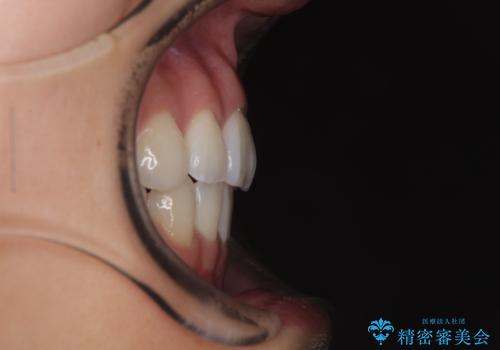

- 前歯が突出して、眠るときに口が開いてしまうことを気にして来院された患者様です。

横から見た際の口元の飛び出した印象も改善したいとのことで、上下左右の第一小臼歯4本を抜歯し、ワイヤー装置にて抜歯矯正を行うこととしました。

舌の突出癖改善のためのトレーニングをしっかりと実践してくださり、2年強の治療期間でしっかりと仕上げることができました。